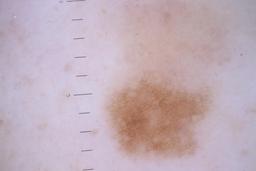

ISIC_5852089

Clinical

| image_type | dermoscopic |